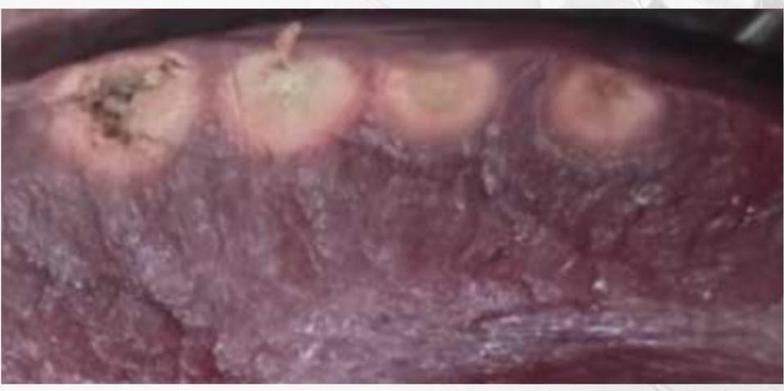

当电流通过阻抗介质时,电压降低,产生热量,类似电热毯、微波炉加热。射频消融是指消融导管经过动脉/静脉到达靶组织,射频电流流经该阻抗组织产生热量,使心肌细胞变性、坏死。

组织加热过程包括阻抗热和传导热。阻抗热损伤深度1-3mm,传导热损伤深度通常3-7mm。组织温度超过50℃,心肌细胞发生不可逆性损伤。